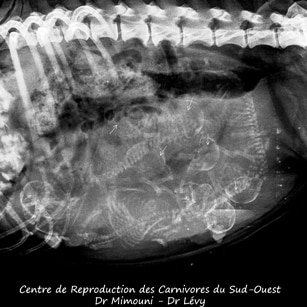

3. La radiographie : pour le comptage précis des chiots dès J45

La radiographie abdominale n’est utilisable qu’à partir du 45e jour de gestation. Avant cette date, le squelette fœtal n’est pas encore ossifié et les chiots ne sont pas visibles à la radio. C’est pourquoi cet examen est principalement utilisé dans les 10 derniers jours de gestation, pour :

- déterminer avec précision le nombre exact de chiots à naître — information cruciale pour surveiller que tous les fœtus ont bien été expulsés lors de la mise bas ;

- évaluer la taille des fœtus par rapport au bassin maternel (pertinent pour les races à risque obstétrical).

Fiabilité : Excellente pour le comptage des chiots à partir de J50. Cependant, des fœtus superposés peuvent parfois fausser le décompte.

Innocuité : L’exposition aux rayons X lors d’une radiographie vétérinaire est très faible et sans danger démontré pour les fœtus en fin de gestation. Cet examen n’est cependant pas recommandé en début de gestation.

Coût approximatif : entre 60 et 100 €.